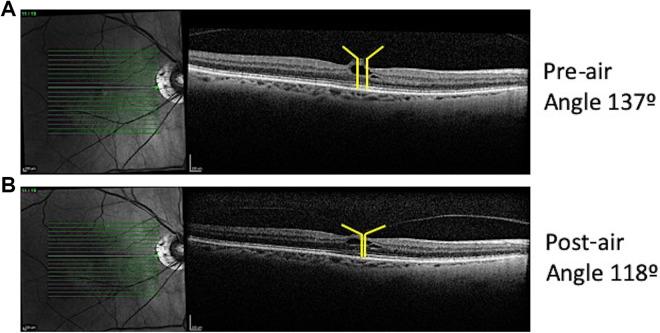

We conducted a retrospective consecutive case series of 20 eyes from 19 individuals with focal VMT who underwent pneumatic vitreolysis with intravitreal air (January 2017 to November 2018). We analyzed patients via spectral-domain optical coherence tomography before intravitreal air injection and at 1 month. The primary outcome measure was release of VMT.

We observed release of VMT in 55% of individuals. An analysis limited to phakic eyes demonstrated release of VMT in 69%, and 65% developed improved best-corrected visual acuity. Individuals with persistent VMT and visual improvement had a significant reduction in angle of vitreoretinal insertion ( < .01), area under VMT ( < .05), and subfoveal cyst area ( < .05).

Intravitreal air is an effective treatment for focal VMT. In individuals with persistent VMT, visual-acuity improvement was associated with a reduction in overall VMT.